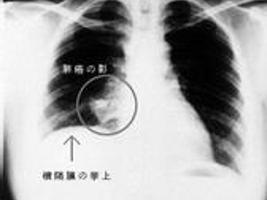

1. 非小细胞肺癌的早期诊断主要依靠以下指标:(1)年龄>45岁,有长期吸烟史或不良空气环境下工作或生活史。 (2)临床症状:咳嗽、咯血、胸痛、胸闷不适、肺部炎症、呼吸困难、上腔静脉综合征(上肢水肿或面部水肿)、肺外表现(关节疼痛不适、抗利尿激素分泌异常综合征等)。. 目前用于肺癌早期的筛查方法主要有影像学检查、痰脱落细胞学检查、支气管镜检技术以及生物标志物等。 影像学检查方法 胸部x线检查是传统的影像学检查手段,能够观察胸部结构的整体,但分辨率较低、易漏诊。. 怎么判断是不是得了肺癌,得了肺癌怎么办,现在空气质量越来越差,雾霾横行,纵使一直以来对于肺癌的研究和预防从未松懈,但是肺癌的发生率和致死率也一直长居不下,然而早期诊断肺癌对于预后还是有不可轻视的作用的,下面就谈谈关于肺癌的有关知识。.

肺癌是发病率和死亡率增长最快,对人群健康和生命威胁最大的恶性肿瘤之一。近50年来许多国家都报道肺癌的发病率和死亡率均明显增高,男性肺癌发病率和死亡率均占所有恶性肿瘤的第一位,女性发病率占第二位,死亡率占第二位。肺癌的病因至今尚不完全明确,大量资料表明,长期大量吸烟与. 国际早期肺癌行动计划 (2005) 采用低剂量螺旋ct对无症状高危人群筛 查发现了458例肺癌 其中80% 为i期 行手术治疗的肺癌患者8年生存率为95-98% 早期诊断—影像学检查 pet (正电子发射断层扫描) ct?. 统计数据显示,25%的肺癌患者在被诊断出肺癌时是没有特异性症状的,许多是出于其他原因进行ct或x线检查才发现的。 肺癌早期诊断 目前我国肺癌患者人数由于种种原因处在增长期,早筛对于患者的生存率意义重大,对早期临床症状的重视能够挽救患者的生命。. 肺癌是全球和中国发病率和死亡率排名第一的恶性肿瘤,中国面临的肺癌负担尤其严重。据统计,截至2019年,我国肺癌患者5年生存率约为19. 7%,低于20年前美国和日本的水平。而美、日等发达国家的肺癌患者生存率较高,主要得益于早期筛查。研究.

因此,早期诊断在提高肺癌患者生存率、节省治疗开支等方面都能带来重大利好。日前,在江苏常熟的第16届国际呼吸病学术年会现场,雅培宣布加入国际智能健康联盟,并与中国肺癌防治联盟签署重要战略合作。. 还有一点必须知道,肺癌早期可以没有任何症状,有的人只是在健康体检中偶然发现肺部结节,然后进一步检查诊断为肺癌。因此,早期发现肺癌,更重要的是进行肺癌筛查,推荐肺癌高危人群每年做一次低剂量螺旋ct检查。. 肺癌的早期诊断. 肺癌的早期诊断依赖于每年的健康体检,尤其是长期吸烟的病人,建议40岁以上每年进行健康体检,接受胸部ct检查。如果胸部ct发现≥1cm左右的磨玻璃结节,建议手术治疗。如果见于≥5mm的磨玻璃结节,建议每3个月随诊。.

肺癌要想有一个正确的诊断,那是少不了临床的一些检查手段,一般来说一个肺癌患者要做足如下几类检查才能进行确证,它们是:肿瘤标记物检查、血液生化检查、影像 肺癌的病理特点. 肺癌早期诊断 肺癌的分布情况右肺多于左肺,下叶多于上叶。. 起源于主支气管、肺叶支气管的肺癌称为中央型肺癌。. 起源于肺段支气管远侧的肺癌,位于肺的周围部位者称为周围型肺癌 肺癌骨. 早期肺癌诊断方法有什么 肺癌在我国的发病率逐年提高,由于早期症状不明显,很多患者就诊时已经到了中晚期,严重影响预后。 近几年,肺癌早期诊断技术不断.